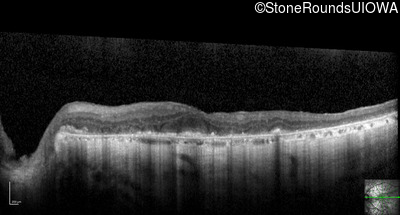

Optical Coherence Tomography - Left - 20/200 -2

Exemplar / OCT Stack